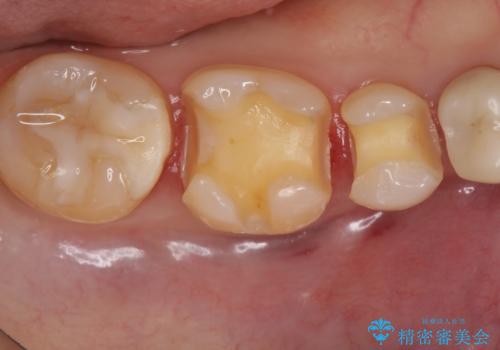

- 口を開けた時、銀の詰め物が目立つとのことで来院。

拡大鏡下で詰め物を外し、う蝕がない事を確認して、セラミック(e-maxインレー)で治療を行いました。

銀の詰め物は歯質との間の隙間ができやすく

虫歯の再発リスクが高いです。

セラミックの詰め物(e-maxインレー)は歯質との隙間ができにくく

虫歯の再発リスクが低くなります。